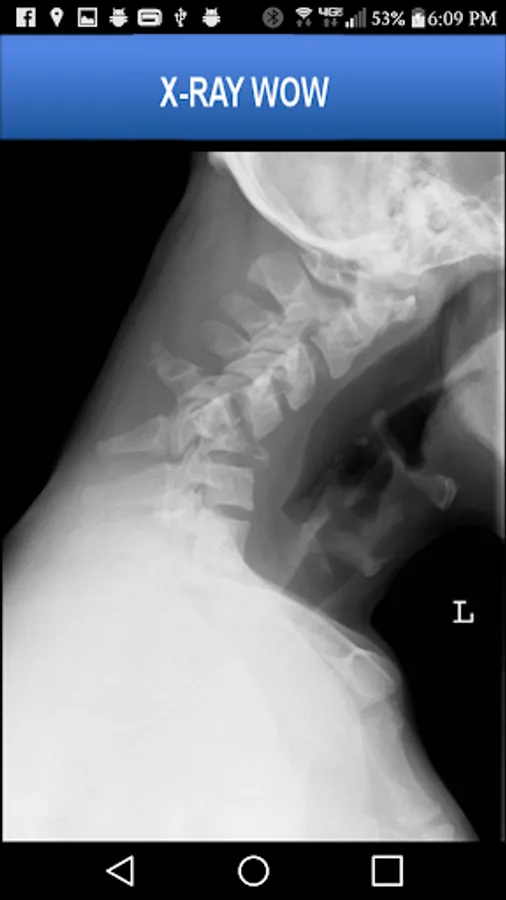

A collection of authentic x-ray images of 20 patients who have experienced serious trauma or unusual surgical procedures.

More than 55 x-ray images are included, many pointing out pathology using arrows and lines. The images may be pinch-zoomed.